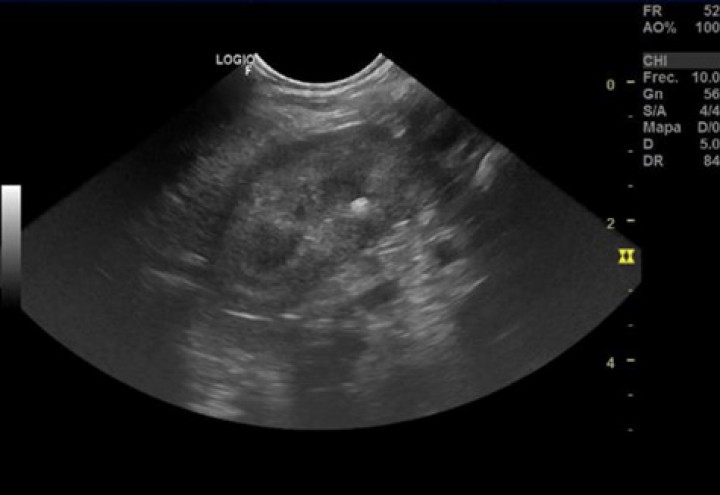

En este caso al no disponer en nuestro centro de los medios endoscópicos necesarios y de la urgencia del proceso, se optó por la realización de una cistotomía ventral (Fig. 4). Se repitió el análisis bioquímico preoperatoriamente, siendo todos los valores normales excepto un aumento leve de la uremia (BUN: 29 mg/dl; valor de referencia: 7-27 mg/dl). Se realizó un abordaje abdominal ventral parapeneano derecho y se realizó una cistotomía longitudinal ventral. La exploración vesical confirmó la presencia intravesical de una espiga de 1,7 cm de longitud, confirmando un diagnóstico de cuerpo extraño vesical.

<p>(<strong>A</strong>) Exposición de la vejiga de la orina mediante abordaje parapeneano para el procedimiento quirúrgico. (<strong>B</strong>) Momento intraquirúrgico de extracción del cuerpo extraño a través de la cistotomía realizada. (<strong>C</strong>) Detalle intraquirúrgico del aspecto del cuerpo extraño (espiga) extraído.</p>

Figura 4

(A) Exposición de la vejiga de la orina mediante abordaje parapeneano para el procedimiento quirúrgico. (B) Momento intraquirúrgico de extracción del cuerpo extraño a través de la cistotomía realizada. (C) Detalle intraquirúrgico del aspecto del cuerpo extraño (espiga) extraído.

Se realizó el cierre de la cistotomía mediante sutura multifilamento, absorbible, de ácido poliglicólico (Safil®, Braun, Barcelona), realizando una sutura monocapa con patrón continuo en aposición. El cierre de la laparotomía se llevó a cabo por capas, mediante una técnica habitual.